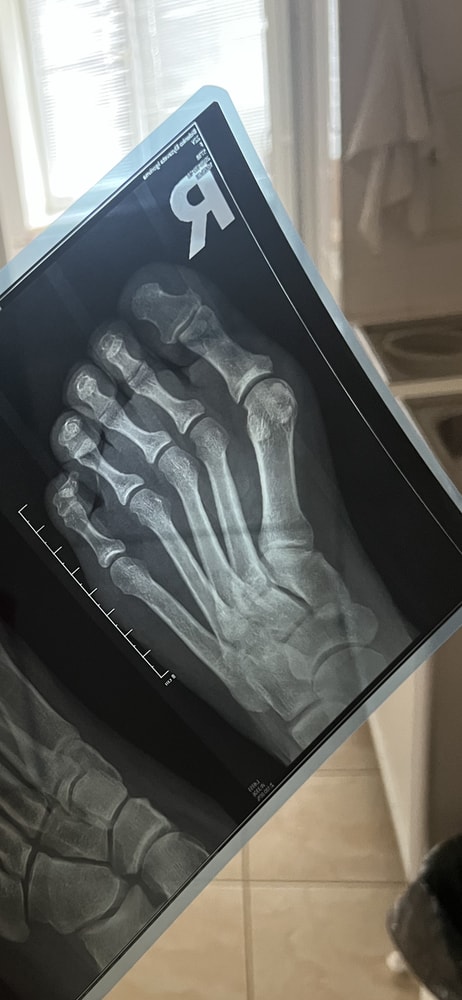

Вопрос больше по ортопедии

Если ли тут трещина 2,3 палец ?? Очень сильно опухло , гематома ступать больно . А к врачу в понедельник. Травмпункт ужасный